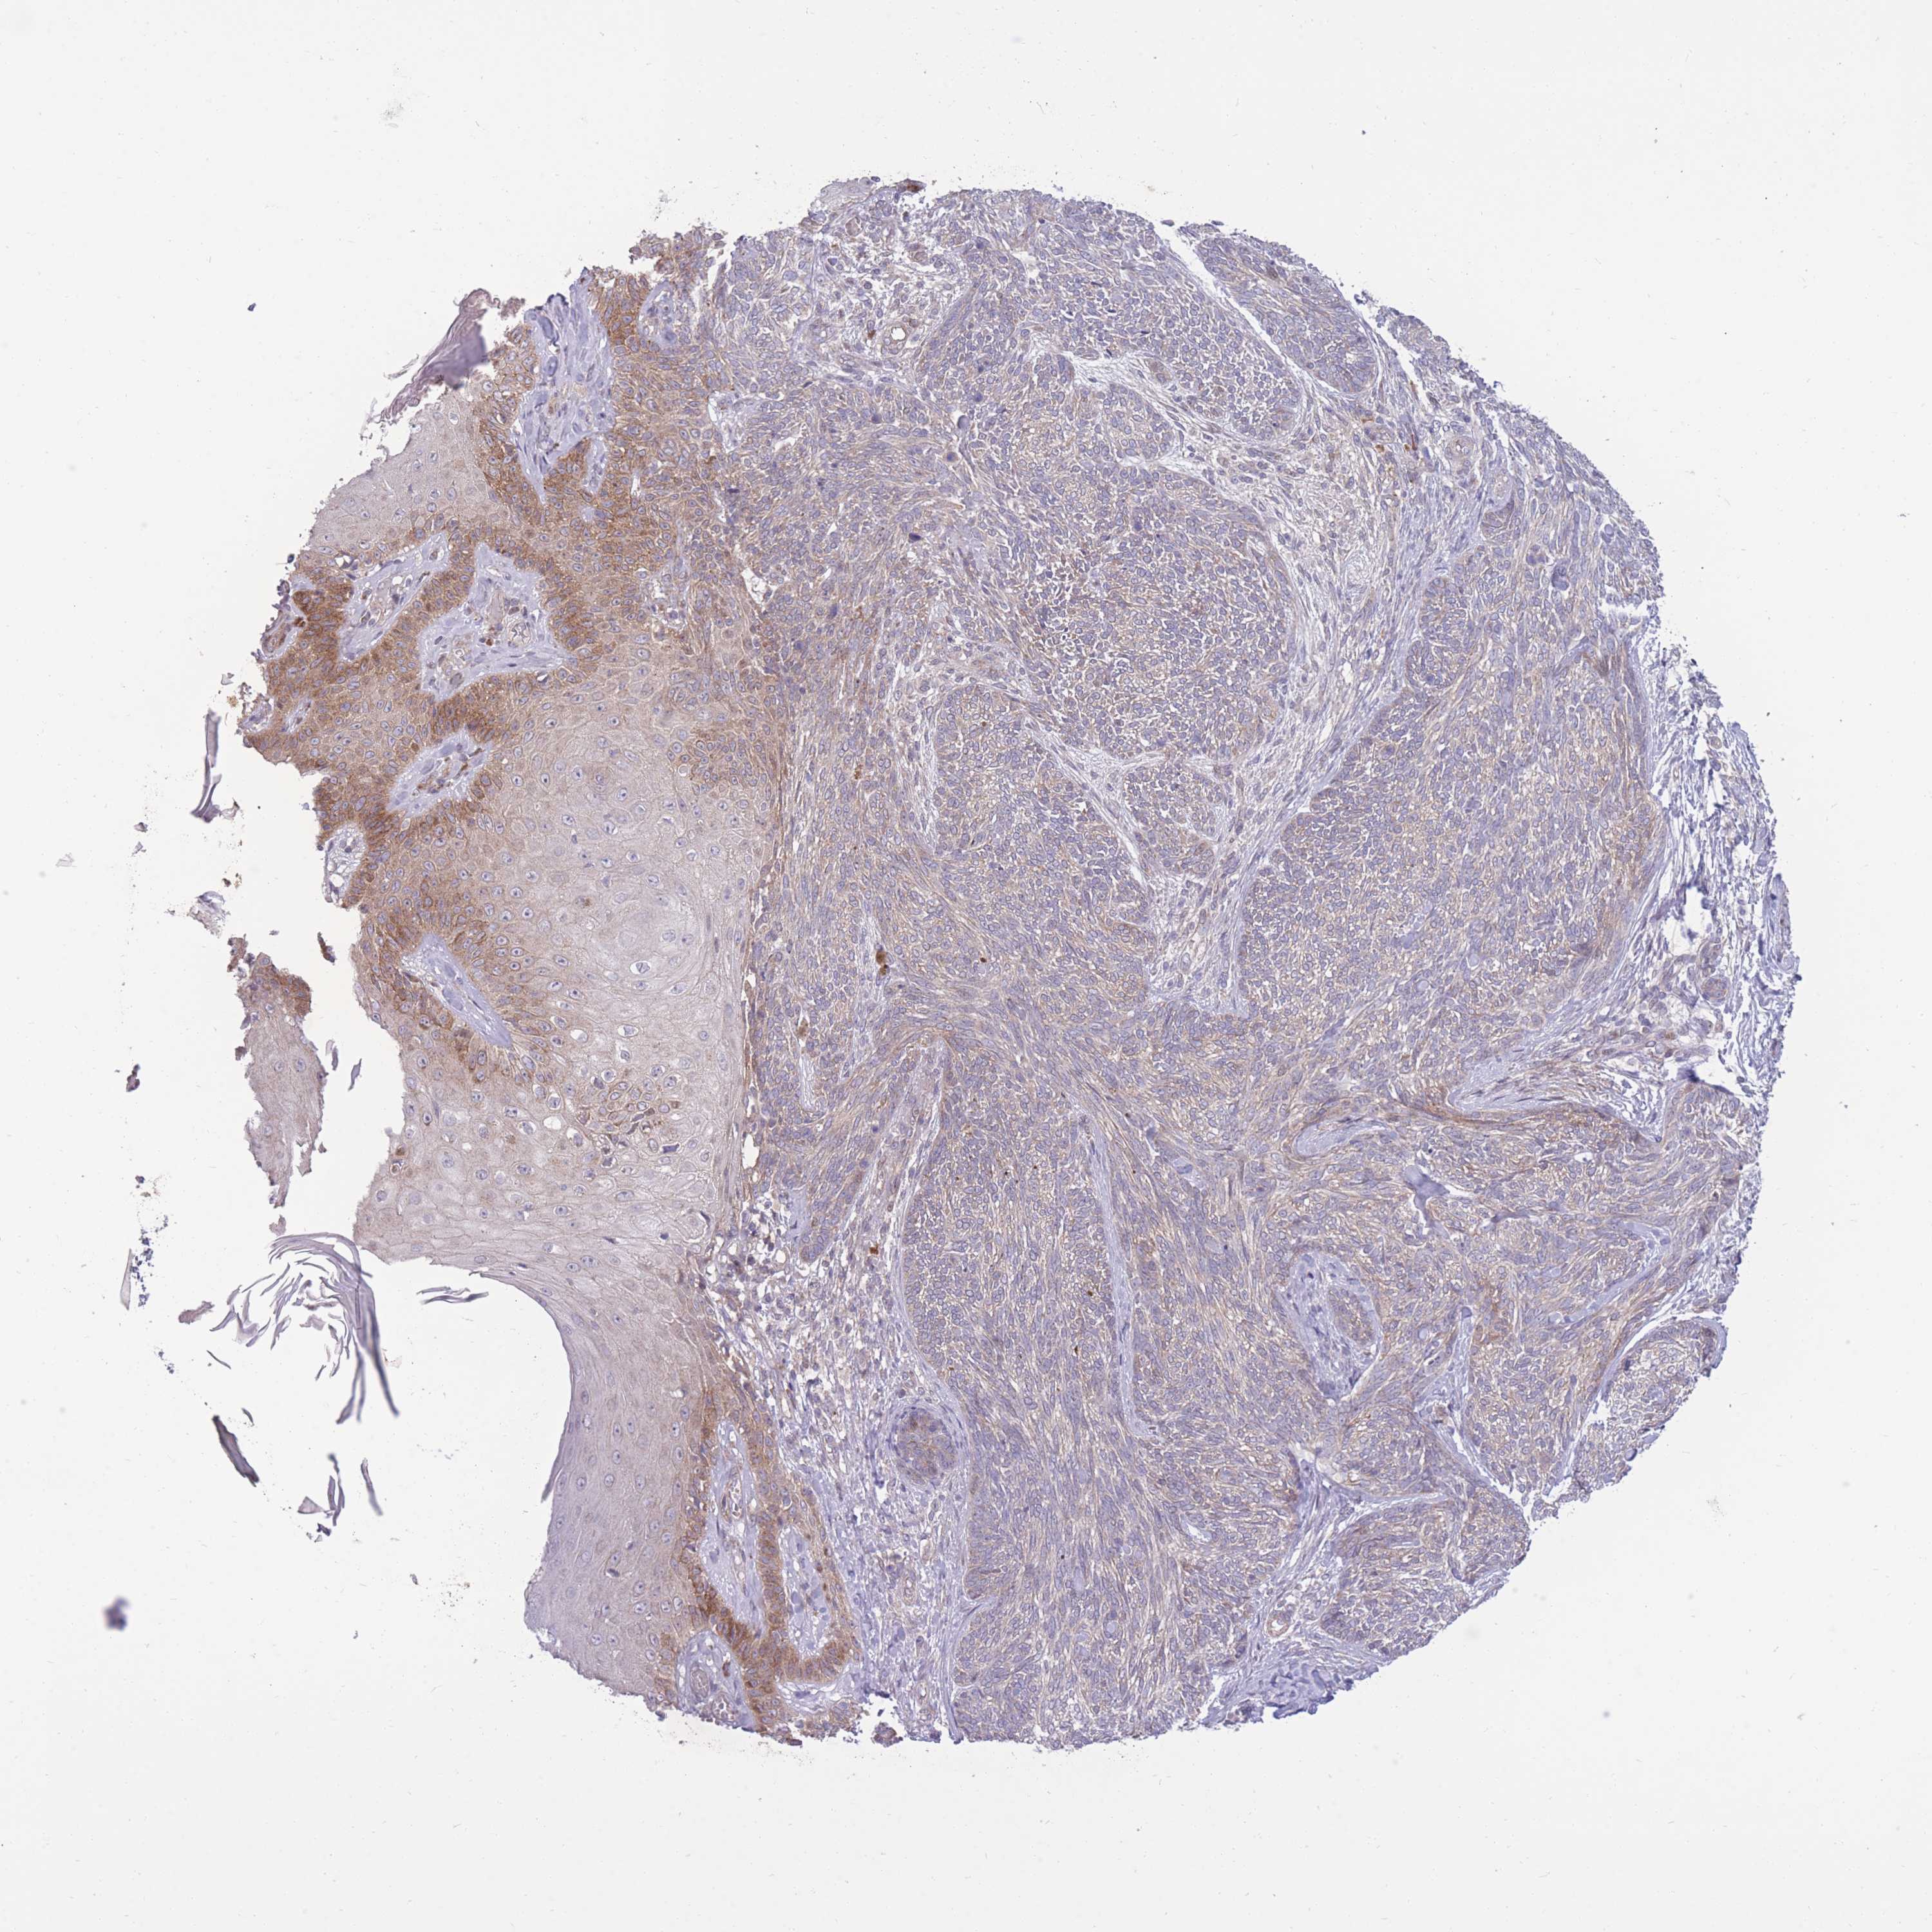

SKIN CANCER - Protein expressioni

A mouse-over function shows sample information and annotation data. Click on an image to view it in a full screen mode. Samples can be filtered based on level of antibody staining by selecting one or several of the following categories: high, medium, low and not detected. The assay and annotation is described here.

Antibody staining in the annotated cell types in the current human tissue is reported as not detected, low, medium, or high, based on conventional immunohistochemistry profiling in selected tissues. This score is based on the combination of the staining intensity and fraction of stained cells.

Each image is clickable and will lead to virtual microscopy that enables deeper exploration of all samples and also displays staining intensity scores, fraction scores and subcellular localization as well as patient and tissue information for each sample.

Antibody HPA041491

Basal cell carcinoma